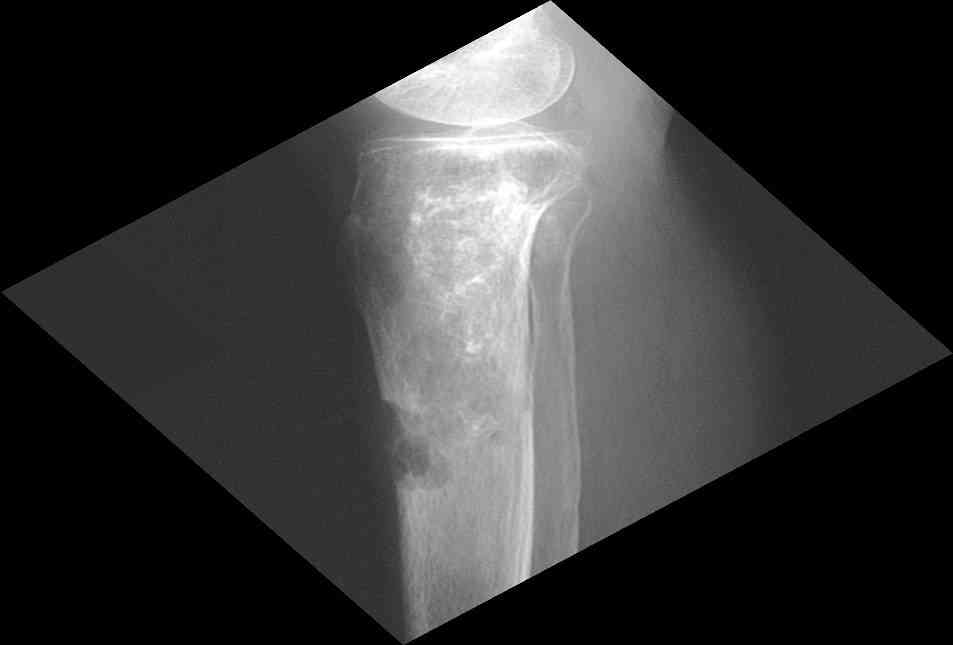

Представленные Вами данные о пациенте 57 дет с болезнью Альбертс-Шенберга чрезвычайно интересны, но диагноз вызывает большие сомнения. Для мраморной болезни характерно прееобладание склероза, а на представленных рентгенограммах преобладает симметричная дезорганизация архитектоники губчатой кости в эпиметафизарной зоне дистальных отделов бедер и голеней.

Мне кажется, представленные рентгенограммы скорее соответствуют варианту фиброзной дисплазии который был описан М. Campanacci (1976) или

обызвествляющей фиброме H.E.Schlitter (1958).

Уважаемый Константин Иванович! Полностью согласен с проф. Михайловым, данный случай не похож на мраморную болезнь, при которой имеется резкое, строго симметричное и генерализованное уплотнение костной ткани (остеопетроз), и кость оказывается построенной преимущественно из гомогенного компактного костного вещества. Для примера привожу случай из архива нашего института (бедренные, плечевые кости и таз, рис 1,2,3)

Изменения структуры костей у Вашего пациента больше похожи на полиоссальную форму фиброзной дисплазии или болезнь Педжета, возможены также инфаркты костного мозга б.берцовых костей. К сожалению, качество снимка не очень хорошее, непонятно, сохранен ли кортикальный слой б.берцовых костей по передней поверхности.

Для примера привожу случай из архива американской ассоциации рентгенологов (ACR) - развитие злокачественной фиброзной гистиоцитомы на левой б.берцовой кости у пациента с множественными инфарктами костного мозга (рис 4,5 - левая, рис 6 - правая)

Не являюсь специалистом по костной патологии, но мне кажется, на ренгенограмме множественные мета-диафизарные образования напоминяющее змееподобных извилистых линии и периостеальные ламинирование очень напоминяет картину остеонекроза (инфаркта) костей, возможно связано с длительным применением стероидов.

слайды из прошлегодного случая.